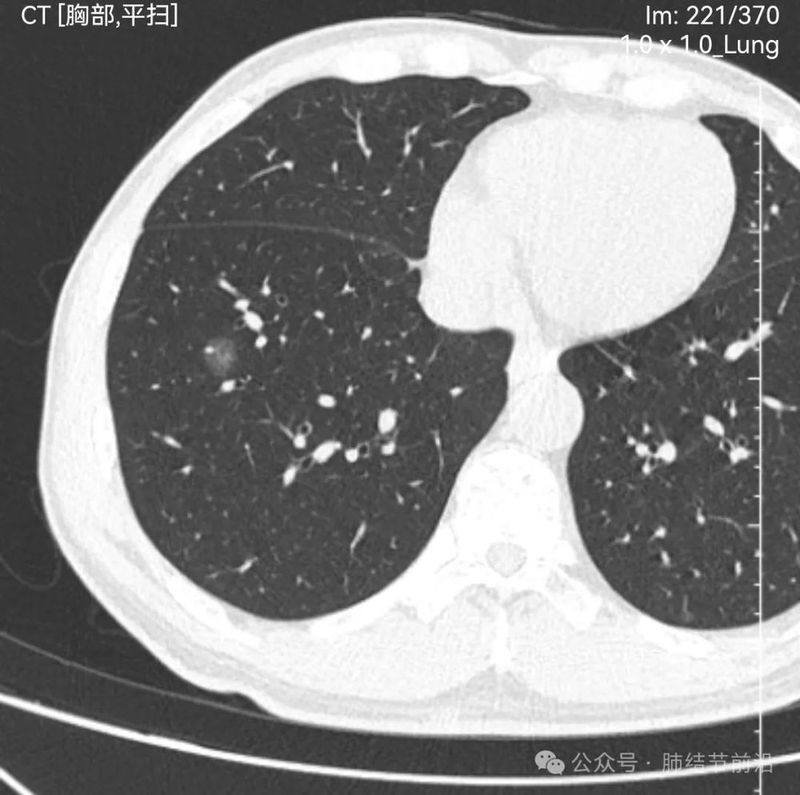

61岁女性,无吸烟史,2024年7月行冠脉CT时发现右肺下叶磨玻璃结节14mm。后续马上复查肺部薄层CT。

见右下肺纯磨玻璃结节14mm。有“血管穿过”、空泡。磨玻璃边界清楚而不毛糙。形态上是典型的肿瘤性磨玻璃,以微浸润腺癌可能大。